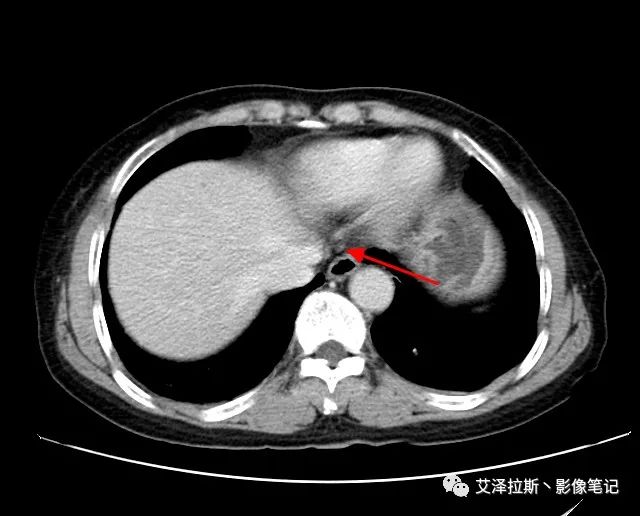

【影像所見】 胃竇部狹窄,胃壁環形增厚,小彎側見一巨大潰瘍,周圍伴“環堤征”,漿膜面不完整,胃周脂肪見網格狀條索影,病灶與肝臟左葉、胰腺鉤突脂肪間隙消失,增強掃描病灶明顯強化。引流區內約15個區域淋巴結受累。

【診斷意見】 胃竇部胃癌(T4N3期) 該病例腫塊突破漿膜層,與肝臟左葉、胰腺鉤突分界不清,脂肪界面消失,定為T4期; 受累及的淋巴結為15個區域,定為N3; 有無遠處轉移尚不明確,所以M期暫時無法確定。